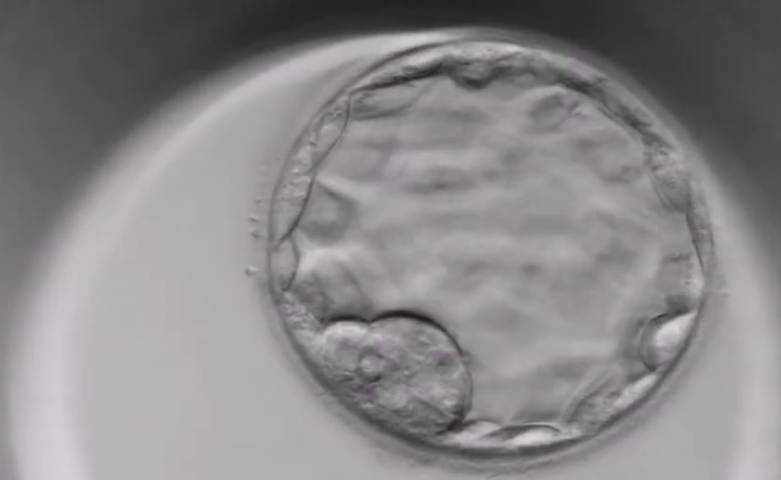

Při IVF se embryo do dělohy přenáší obvykle ve stádiu blastocysty, tedy pět až šest dní po oplodnění vajíčka spermií. Následující dny jsou klíčové – rozhodují o tom, zda dojde k úspěšnému uhnízdění (nidaci) a těhotenství se začne vyvíjet.

Embryo, nyní ve stádiu blastocysty, se nachází v děloze a pomalu se začíná „líhnout“ (proces hatchingu) z ochranného obalu. Tento krok je nezbytný pro to, aby se mohlo přichytit na děložní sliznici (endometrium).

Líhnutí blastocysty pokračuje a embryo se začíná jemně přichytávat na endometrium. Je to první signál, že by mohlo dojít k implantaci.